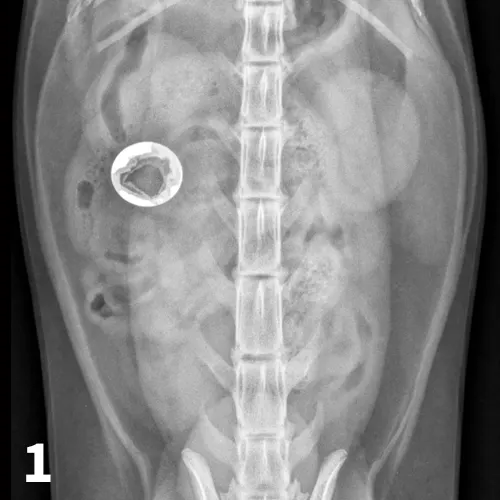

Figure 5A depicts a left lateral abdominal radiograph of a dog with a pyloric foreign body. Figure 5B depicts a right lateral abdominal radiograph of a dog with a pyloric foreign body.

FIGURE 5

Left lateral radiograph (A) of a 4-year-old crossbreed dog with a 3-day history of vomiting and anorexia. An irregularly marginated, well-defined, soft tissue opaque structure (arrows) outlined by gas is present within the pylorus on the left lateral view. A right lateral radiograph of the same dog (B). The irregularly marginated, well-defined, soft tissue opaque structure displayed in Figure 5A is not clearly seen on the right lateral view because of the dependent distribution of fluid into the pyloric antrum silhouetting with the foreign body. This was confirmed to be cloth causing a gastric outflow obstruction.